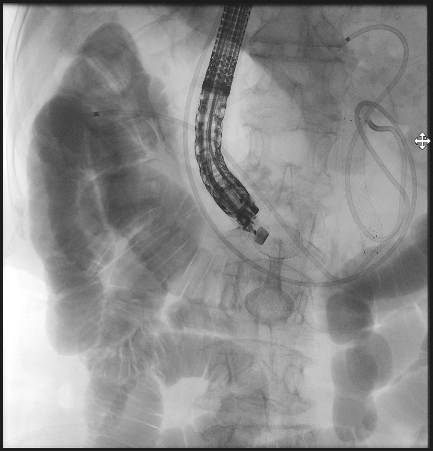

超声内镜探头如同高精度的“GPS导航”,在胃腔内实时扫描,清晰显示出肿瘤的边界、周围血管的搏动,以及最佳“桥墩”定位点。

在超声的实时引导和X光造影的监控下,穿刺、导丝置入、支架释放……

一系列步骤如行云流水。

当那枚双蘑菇头支架在胃与空肠之间成功展开,宛如一朵生命之花在体内绽放,一座避开所有险滩的“人工桥梁”就此贯通。